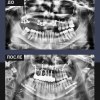

Случай был крайне сложным: после удаления новообразования требовалось восстановить более половины верхней челюсти. Но для нас нет нерешаемых задач!

▪️ Микрохирургическая реконструкция больше половины верхней челюсти: удаление новообразования, одномоментное закрытие дефекта малоберцовым аутотрансплантатом.

▪️ Ортодонтическая подготовка: установка имплантов в трансплантат и временных ортопедических конструкций.

▪️ Ортогнатическая хирургия: точное перемещение всей челюсти для идеальной функциональности и формирования правильного прикуса.

▪️ Тотальное протезирование: кропотливое моделирование и создание эстетичного зубного ряда на основе полной цифровой диагностики.